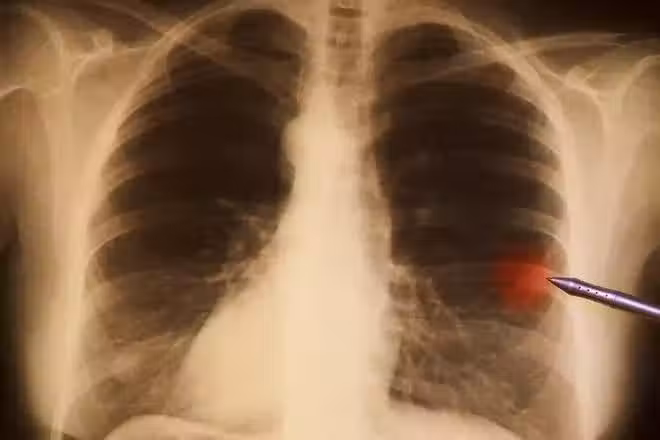

然而癌症卻還是盯上了他 ,2007年,寫完《中國新革命》,他 突然 暈倒 ,妻子陪著去做檢查,結果發現是肺癌晚期,全身多處有陰影,癌細胞已經向各處擴散,醫生說 要做好思想準備,可能活不過三個月。

凌志軍很是不解,自己已經有注意,而且平日身體都很硬朗,怎麼就突然成了肺癌晚期。